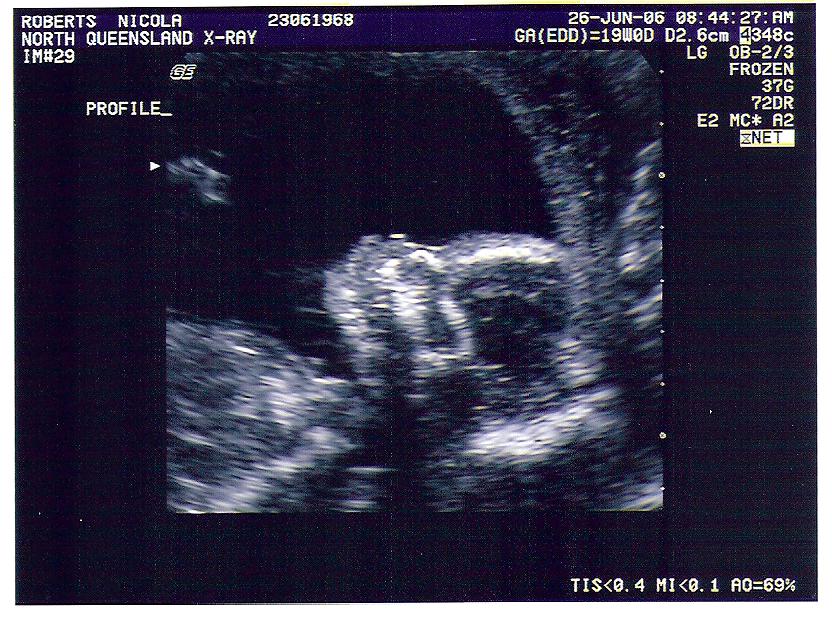

Chromie 19 Weeks Shots

These pictures just don't do him justice. Scan went very well. Kiddo was "very good" and didn't dance around too much to get all the important shots. He's gonna be tall and good looking, extremely intelligent and love fishing! So we were told.